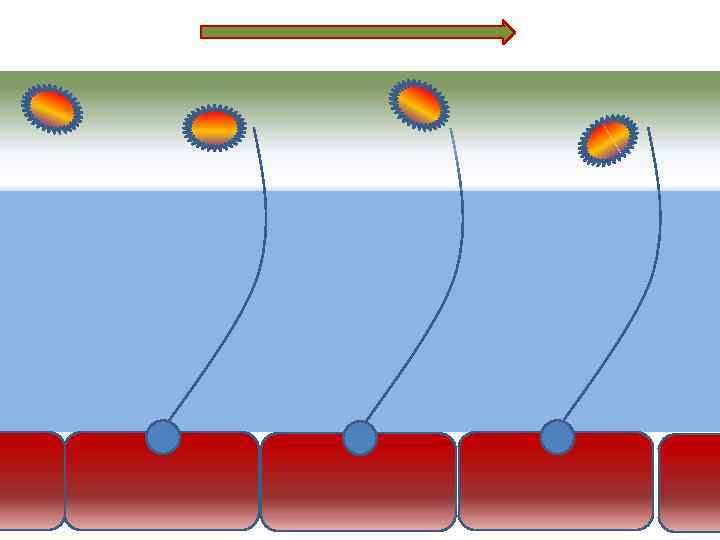

Факторы риска Недостаточное увлажнение дыхательной смеси • естественное удаление бактерий • состояние эпителия трахеи и бронхов

Факторы риска Недостаточное увлажнение дыхательной смеси • естественное удаление бактерий • состояние эпителия трахеи и бронхов

Оптимальное увлажнение 37°С, 44 мг/л Оптимальная влажность • Уменьшает время нахождения патогенной флоры в легком

Оптимальное увлажнение 37°С, 44 мг/л Оптимальная влажность • Уменьшает время нахождения патогенной флоры в легком

Механизм защиты легкого Слизь (зеленый цвет) нейтрализует и связывает патогенную флору(синий цвет) Слизь – это барьер между клетками и патогенной флорой Слизь – это транспортное средство

Механизм защиты легкого Слизь (зеленый цвет) нейтрализует и связывает патогенную флору(синий цвет) Слизь – это барьер между клетками и патогенной флорой Слизь – это транспортное средство